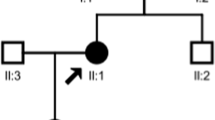

DNA sequencing identified two novel missense variants in SLC12A3 (c.1919A > G and c.2522A > G) in the proband, which resulted in substitution of Asparagine (N) 640 by Serine (S) and of Aspartic acid (D) 841 by Glycine (G), respectively (Fig. 1 and Fig. 2). Moreover, her mother (II2), uncle (II4), and cousin (III3) were the carriers of one variant (p.N640S); whereas her father (II1) was the carrier of the other (p.D841G). No SLC12A3 gene variants were observed in other pedigree members. Both variants were located in the intracellular carboxyterminal domain of the NCC protein (Fig. 3). The pedigree analysis is summarized in Table 2 and Fig. 4. After comparing them with genomic sequence in the Ensemble database (GRCh37.p13), we concluded that this was the first report of these two pathogenic variants.

Pedigree chart of the proband’s family. The arrow indicates the proband. Filled symbols indicate subjects affected by gene mutations (c.1919A > G is marked as black and c.2522A > G is marked as grey). Men are indicated by squares, and women are indicated by circles. III1, the proband, III2, sister, III3, cousin, II1, father, II2, mother, II3, elder uncle, II4, younger uncle